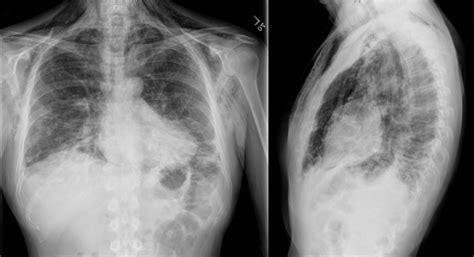

• Imaging: A chest X-ray or CT scan may be used to look for issues in the lungs, esophagus, or aorta.